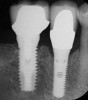

Increasing the number of implants can compensate for decreasing weakness of bone.27 A greater number of implants will provide increased functional loading area and reduced stress on bone. For example, in D2 bone, a pontic may be placed between two implants; whereas, in D3 bone, it may be advantageous to place one implant per tooth (Figure 7).28 In less dense bone, cantilevers should be avoided, and if contemplated, consideration should be given to increasing the number and size of the implants.